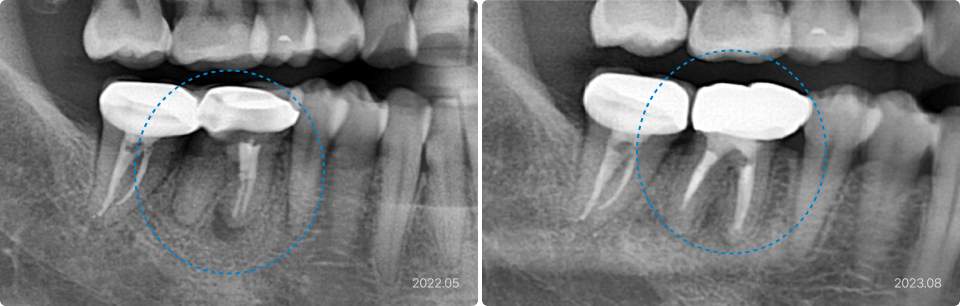

02

타 치과에서 발치 권유 받았으나 재신경치료로 치아 보존

치료 전

치료 후

치료 내용

• 과거 신경치료 불완전으로 재오염과 염증, 통증 발생으로 내원

• 오염된 기존 충전재 제거 후 철저한 신경관 세척, 소독, 밀폐, 충천

• 치료 후 염증과 통증 해소되어 재보철 진행